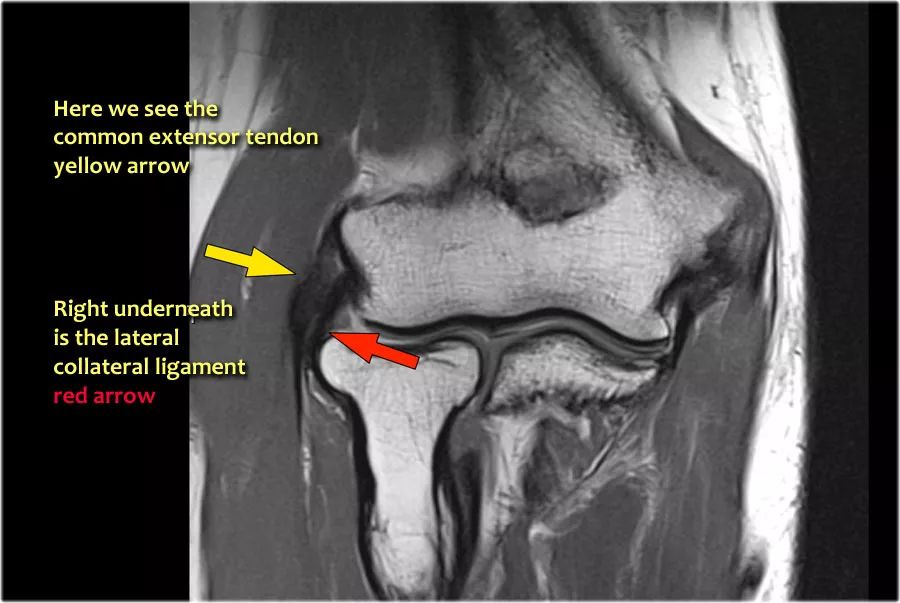

当您寻找桡侧副韧带时,首先要尝试识别常见的伸肌腱,因为在它下面你会发现桡侧副韧带(黄色箭头)。

当你向后走时,你会看到LUCL--侧面尺侧副韧带,它在桡骨头后面扫过(白色箭头)。环形韧带通常难以与RCL区分开,但有时可以在矢状MR-关节造影上识别。